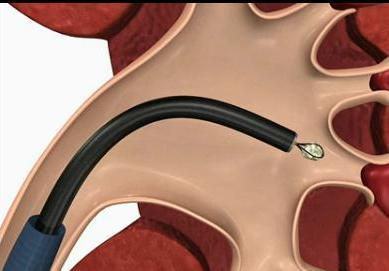

手术当天,在高清电子软镜的引导下,杨泽敏团队开启了一场精准的“体内排雷”。软镜纤细灵活,前端可弯曲,顺着尿道、膀胱、输尿管这一自然通道,轻松抵达肾脏深处,就连最隐蔽的肾盏也一览无余。为避免输尿管损伤,所有操作都在一层“保护套”——输尿管导引鞘内进行。此次手术使用的更是市中医医院特有的“智能武器”:末端可弯曲负压吸引鞘。

当屏幕上的结石清晰可见,钬激光精准出击,将坚硬的结石瞬间粉末化。与此同时,负压吸引装置同步启动,将击碎的结石微粒迅速吸出体外。由于吸引鞘的末端可主动弯曲,医生能轻松调整方向,精准对准目标,大大提高了清石效率。手术全程,肾盂内部始终维持稳定的低压状态,不仅安全,也提升了患者的舒适度。

末端可弯,操作更灵巧:创新的可弯曲吸引鞘,让医生能像使用“机械手”一样,直接控制鞘管前端方向,轻松进入复杂肾盏,减少了组织损伤,缩短了手术时间。